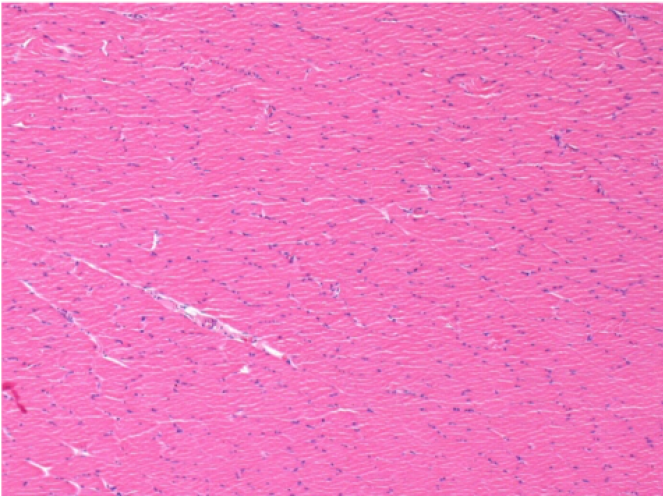

09

7 months after Endopeel Injection

7 months (D210)after Endopeel IM Injection 0.1ml in the right pretibial muscle.

Complete Restitutio ad integrum after 7 months

L : Control-100xD210

R:100xD210

L :Control 50xD210

R50X-D210